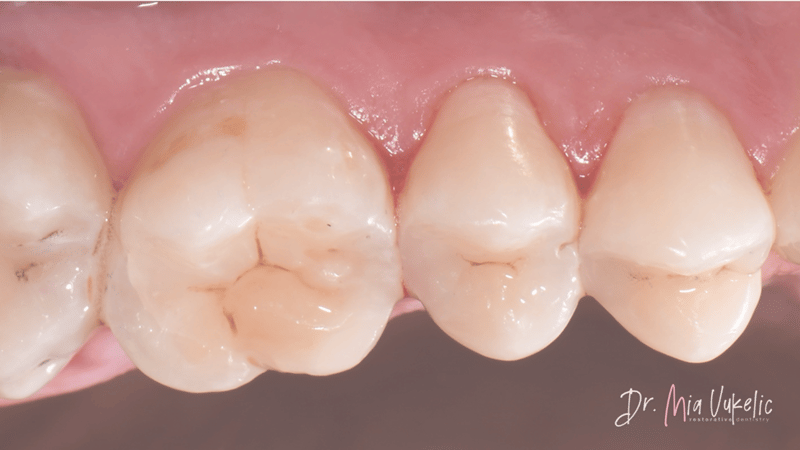

Ästhetische Behandlung der Klasse II von Dr. Mia Vukelić (Case Report)

Der Patient besuchte wurde zur jährlichen Kontrolle vorstellig. Klinische Untersuchungen und Röntgenbilder zeigten Sekundärkaries auf der Okklusalfläche von Zahn 26 sowie kariöse Läsionen an den Distalflächen von 24 und 25. Der Patient hatte keine spezifischen Beschwerden. Die empfohlene Behandlung umfasste eine Klasse I-Restauration an Zahn 26 und Klasse II-Restaurationen an 24 und 25.

Auf den finalen Fotos wird deutlich, dass Transcend Universalkomposit der Restauration ein außergewöhnlich ästhetisches Erscheinungsbild verleiht. Das Halo Teilmatrizensystem ermöglichte zudem die Herstellung einer hervorragenden approximalen Anatomie, wie die Röntgenaufnahme belegt.